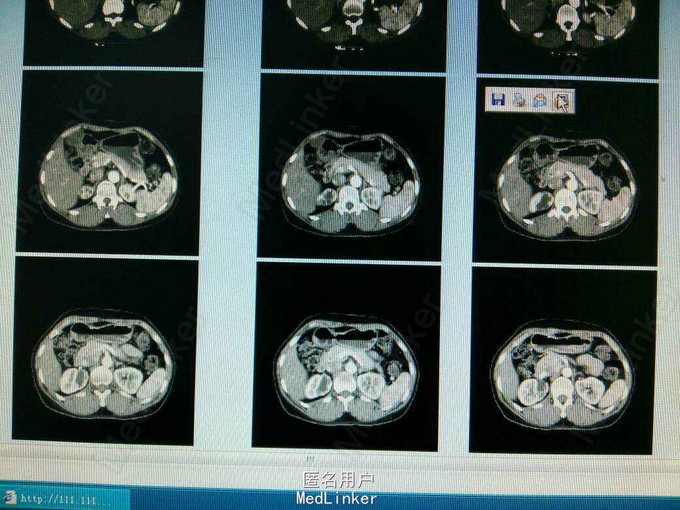

ct提示右侧双肾输尿管畸形,输尿管囊肿。总肾功能正常,尿常规正常,未发现结石等异常,右上位肾脏及输尿管扩张。

如何选择治疗方案?如何处理?是简单处理输尿管囊肿,还是将扩张的输尿管和肾脏一并切除?患者目前无明显不适症状。